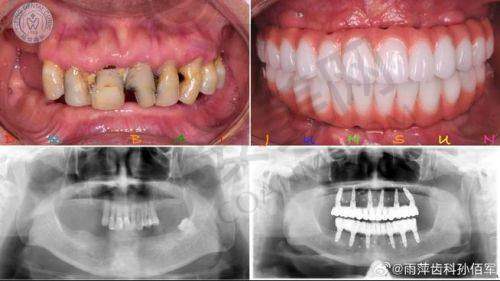

检查结束后,医生根据我的检查结果,为我制定了个性化的全口牙齿种植方案。医生耐心地向我解释了方案的具体内容,包括种植体的选择、种植的步骤、手术的风险以及预期的成效等。他还让我看了一些类似实例的前后对比照片,让我对整个种植过程有了更直观的认识。在这个过程中,我有任何疑问,医生都一一为我解答,让我心里踏实了许多。

成都贝臣口腔医院的全口牙齿种植技术有特别多特色之处。首先,医院采用的是精良的数字化种植技术。通过口腔CT扫描等设备,医生可以严谨地获取患者口腔的三维数据,然后利用计算机软件进行模拟种植,制定出更适合患者的种植方案。这样可以大大提高种植的正确性和成功几率。

经过一段时间的修复,我的全口牙齿种植成效终于显现出来了。现在,我的牙齿看起来非常自然,和真牙几乎没有区别。而且,牙齿的咀嚼功能也得到了较大的修复,我可以像以前一样正常地吃饭了。这让我感到非常开心,生活质量也得到了较大的提高。